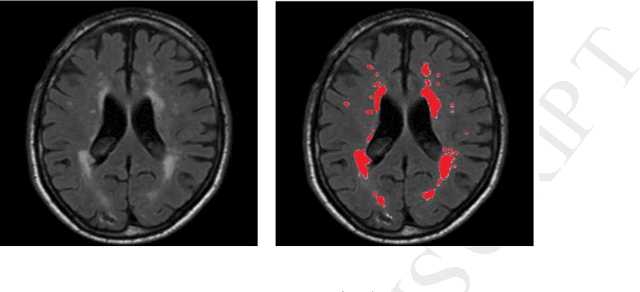

Abstract:White matter hyperintensities (WMH) are commonly found in the brains of healthy elderly individuals and have been associated with various neurological and geriatric disorders. In this paper, we present a study using deep fully convolutional network and ensemble models to automatically detect such WMH using fluid attenuation inversion recovery (FLAIR) and T1 magnetic resonance (MR) scans. The algorithm was evaluated and ranked 1 st in the WMH Segmentation Challenge at MICCAI 2017. In the evaluation stage, the implementation of the algorithm was submitted to the challenge organizers, who then independently tested it on a hidden set of 110 cases from 5 scanners. Averaged dice score, precision and robust Hausdorff distance obtained on held-out test datasets were 80%, 84% and 6.30mm respectively. These were the highest achieved in the challenge, suggesting the proposed method is the state-of-the-art. In this paper, we provide detailed descriptions and quantitative analysis on key components of the system. Furthermore, a study of cross-scanner evaluation is presented to discuss how the combination of modalities and data augmentation affect the generalization capability of the system. The adaptability of the system to different scanners and protocols is also investigated. A quantitative study is further presented to test the effect of ensemble size. Additionally, software and models of our method are made publicly available. The effectiveness and generalization capability of the proposed system show its potential for real-world clinical practice.